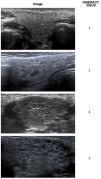

Table 1 presents the results of the ophthalmological evaluation and the salivary gland ultrasound (SGU). Fig. 1 shows the changes observed in the SGUS.

Ultrasound features characteristic of the changes found in the salivary glands of patients with juvenile Sjögren syndrome. All images are of the submandibular gland, and the abnormalities were bilateral. The assessment of the changes on a scale from 0 to 3 was performed using the Salivary Gland Ultrasound Scores (SGUS), a scoring system developed by Outcome measures in Rheumatology (OMERACT) to measure sonographic salivary gland abnormalities in patients with Sjögren syndrome. The analysed variables include the inhomogeneity of the parenchyma, the presence of anechoic/hypoechoic areas (micro- or macrocysts) and the echogenicity of the surrounding tissue (normal or fibrotic).